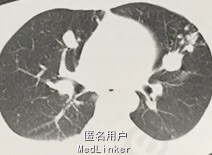

查体:全身皮肤黄染,肺部听诊啰音。CT示肺部散在钙化影,肝区弥漫性占位异常影,密度混杂,大小不一。

诊断为肺结核、肝结核灶。给予抗结核规范化治疗,手术切除残留占位灶。